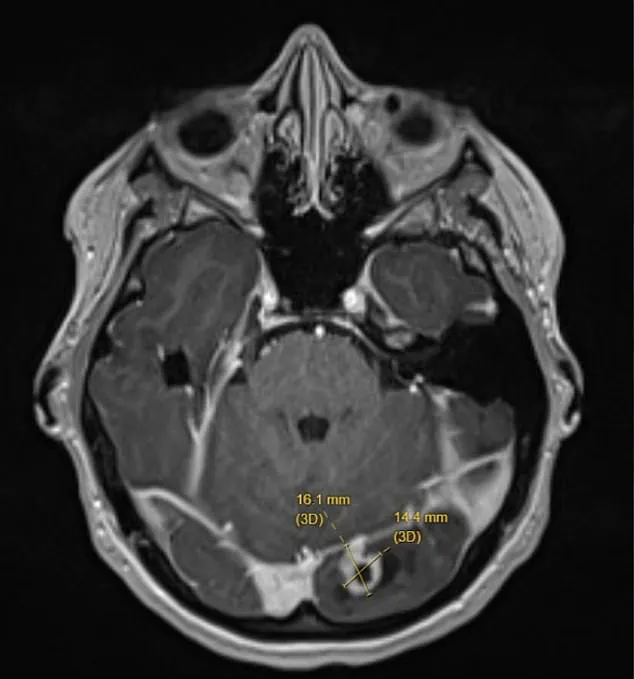

The above is a picture of the scan of Ms Ash’ brain, with the tumor shown by the yellow lines.

Doctors found the tumor on her left occipital lobe — the part of the brain at the back of the head responsible for processing visual information from the right eye.

Fortunately, the mass was not cancerous, but its location explained the strange flashes Ms Ash had been experiencing.

She was rushed to hospital, where imaging scans revealed a marble-sized tumor pressing on her brain.